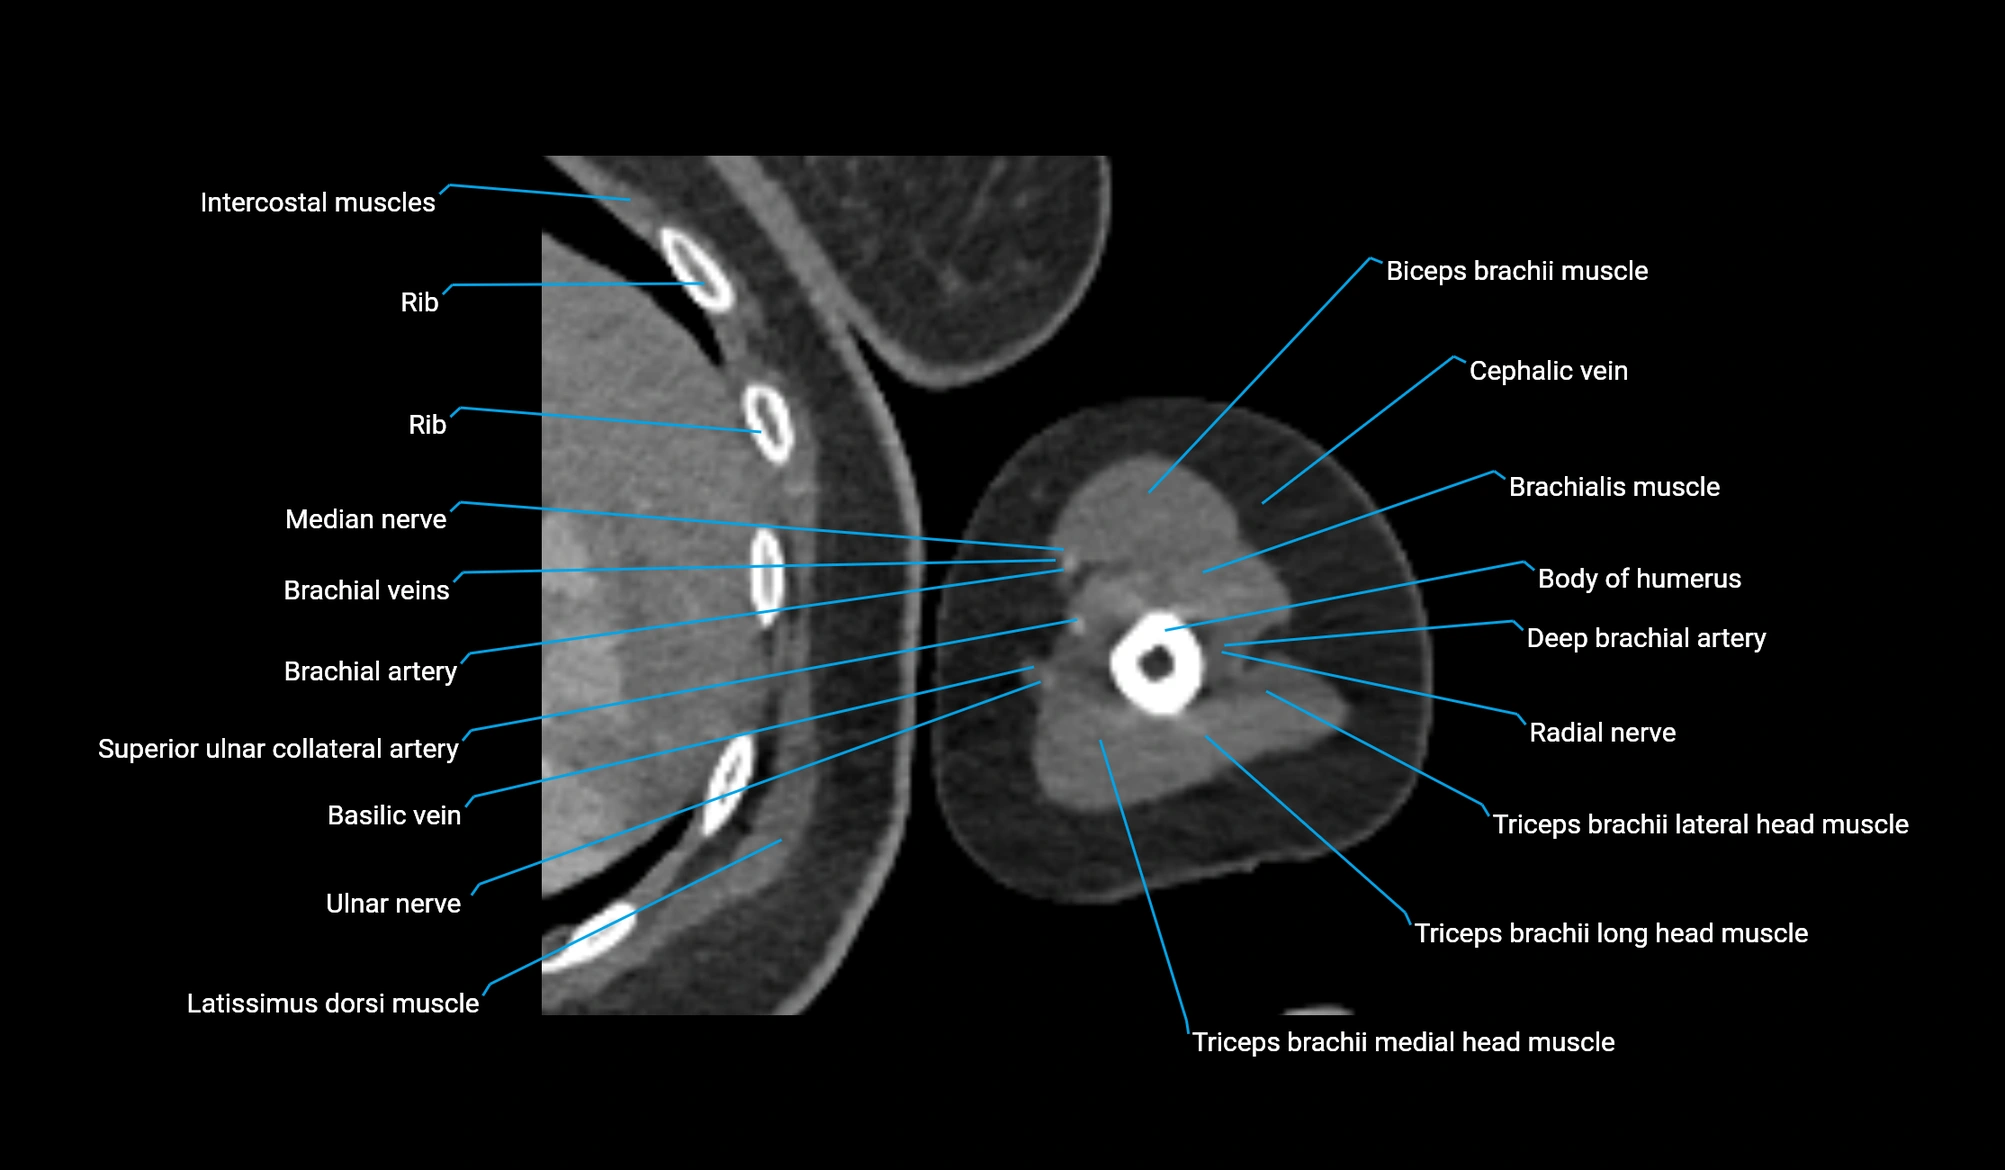

CT image